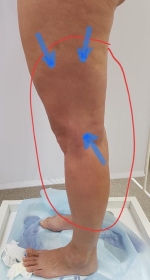

Пьезогенная грыжа

Мышечная грыжа

Псевдовены. Странные образования, располагающиеся по передне-наружной поверхности голени. Может быть одно или несколько. Выглядят как вены. Но только по форме. По цвету как окружающая кожа. Аналогично венам увеличиваются при принятии вертикального положения. Не болят сами по себе и при пальпации. Чаще всего их можно принять за перфорантную вену в этом месте. Картина проясняется при выполнении узи. Мы увидим, что есть отверстие в фасции, и из него при надавливании содержимое выдавливается внутрь, под фасцию. А потом возвращается вновь под кожу. На самом деле это мышечная грыжа, или так называемая пьезогеная грыжа. Кроме внешнего вида пациента ничего не беспокоит, и лишь изредка возникают боли в этом месте. На первом фото внешний вид ноги с такими "венами". На втором вид при УЗИ.